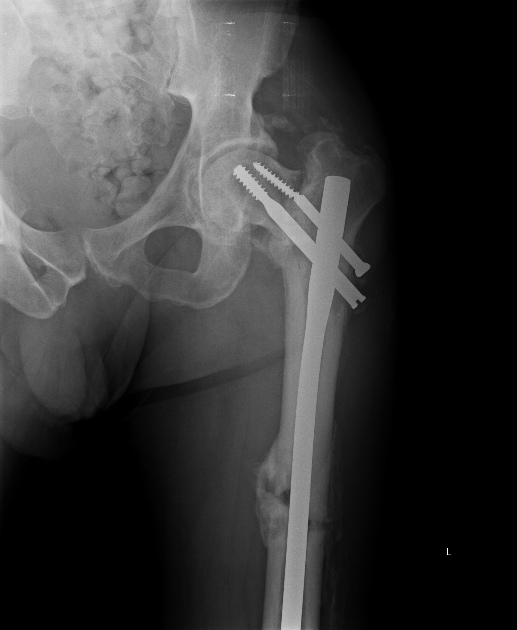

Насчет ревизионного штифтования - вот пример, вчера сделали.

Имя     : 3a.jpg

Тип     : image/jpeg

Размер  : 83792 байтов

Url     : http://weborto.net:8080/pipermail/ortho/attachments/20130531/0a9354ad/attachment-0007.jpg